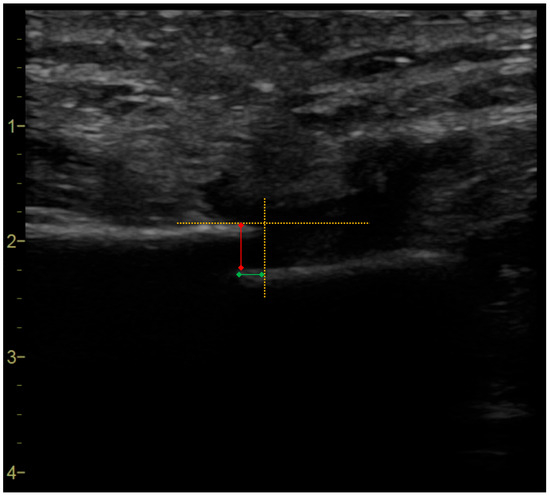

2.3. Real-Time Ultrasound Imaging Acquisition

2.4. Off-Line Ultrasound Imaging Data Elaboration